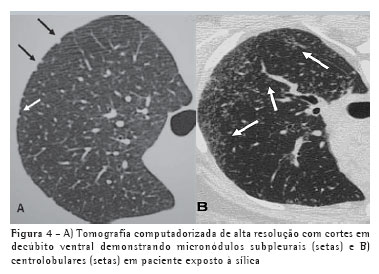

A TCAR é um método mais sensível e específico do que a radiografia simples para a detecção e caracterização da silicose. Permite melhor definição do tipo e da extensão das alterações, especialmente do enfisema centrolobular que pode estar presente nestes indivíduos e que é dificilmente demonstrado pela radiografia, a não ser nos casos mais acentuados. A concordância inter e intraobservador na avaliação das alterações respiratórias decorrentes da silicose é maior com a TCAR do que com a radiografia e a correlação com a função pulmonar é mais fidedigna com a TCAR. Em um estudo realizado num grupo exposto à sílica com radiografias normais, a TC estava alterada em 41% dos casos, sendo que em 10% as alterações eram visíveis apenas com a TCAR.(4) Nos indivíduos com radiografias alteradas, neste mesmo grupo, a TCAR permitiu melhor caracterização dos achados. Por estes motivos, segundo alguns autores, a TC deve ser realizada sistematicamente naqueles indivíduos expostos com suspeita de silicose na radiografia simples de tórax.

Como as alterações predominam nas regiões posteriores, a TCAR deve ser sempre realizada em decúbito ventral, com técnica de alta resolução, cortes finos de 1 a 2 mm, intervalo entre os cortes de 10 mm, e sem injeção venosa do meio de contraste.

Os achados iniciais na TCAR consistem em micronódulos centrolobulares e subpleurais (Figura 4), menores que 0,5 cm. Com a evolução da doença estes micronódulos tendem à confluência, com formação de nódulos maiores (Figura 5), conglomerados (Figura 6) e, numa fase mais tardia, massas fibróticas, geralmente com calcificações e aumento irregular do espaço aéreo adjacente (Figura 7).(5)